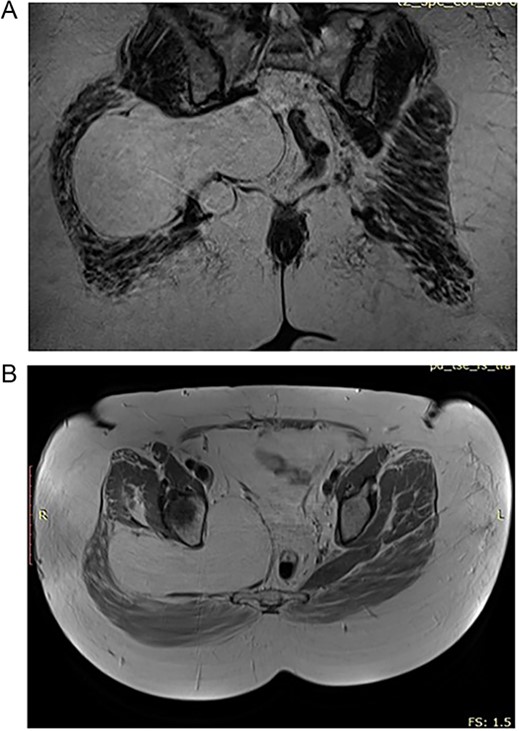

In the 57-year-old female, CT scan revealed a mass inside the pelvis that invades the gluteal musculature (Fig. 1A and B). The mass was homogeneously isointense with fat and ~155×99×148 in size. MRI revealed space-occupying lesions in the right buttock and pelvic cavity, with clear boundaries and smooth edges, not resulting in the displacement of the pelvic organal components.

(A) Preoperative MRT image showing lipoma in the pelvic region. (B) Preoperative CT of the 57 year old patient with high signal of the lipomatous lesion.